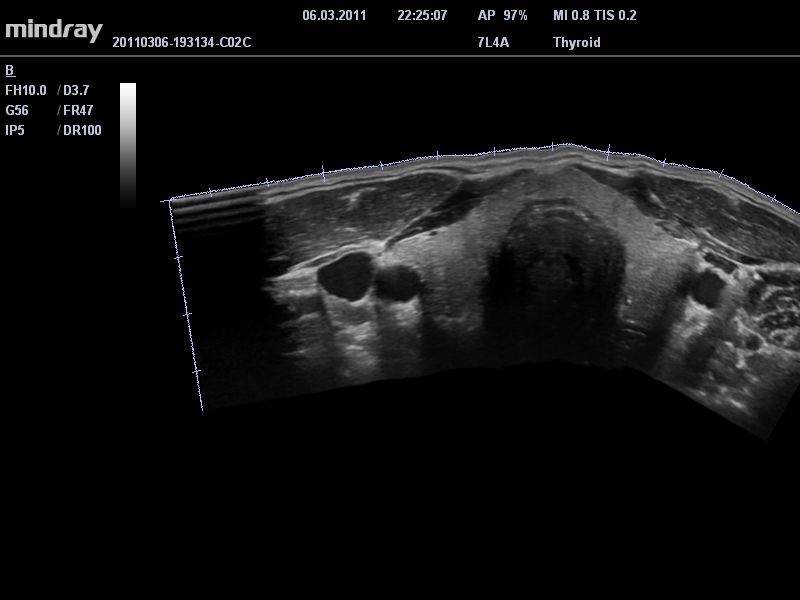

• Линейный ультразвуковой датчик Mindray 7L4A